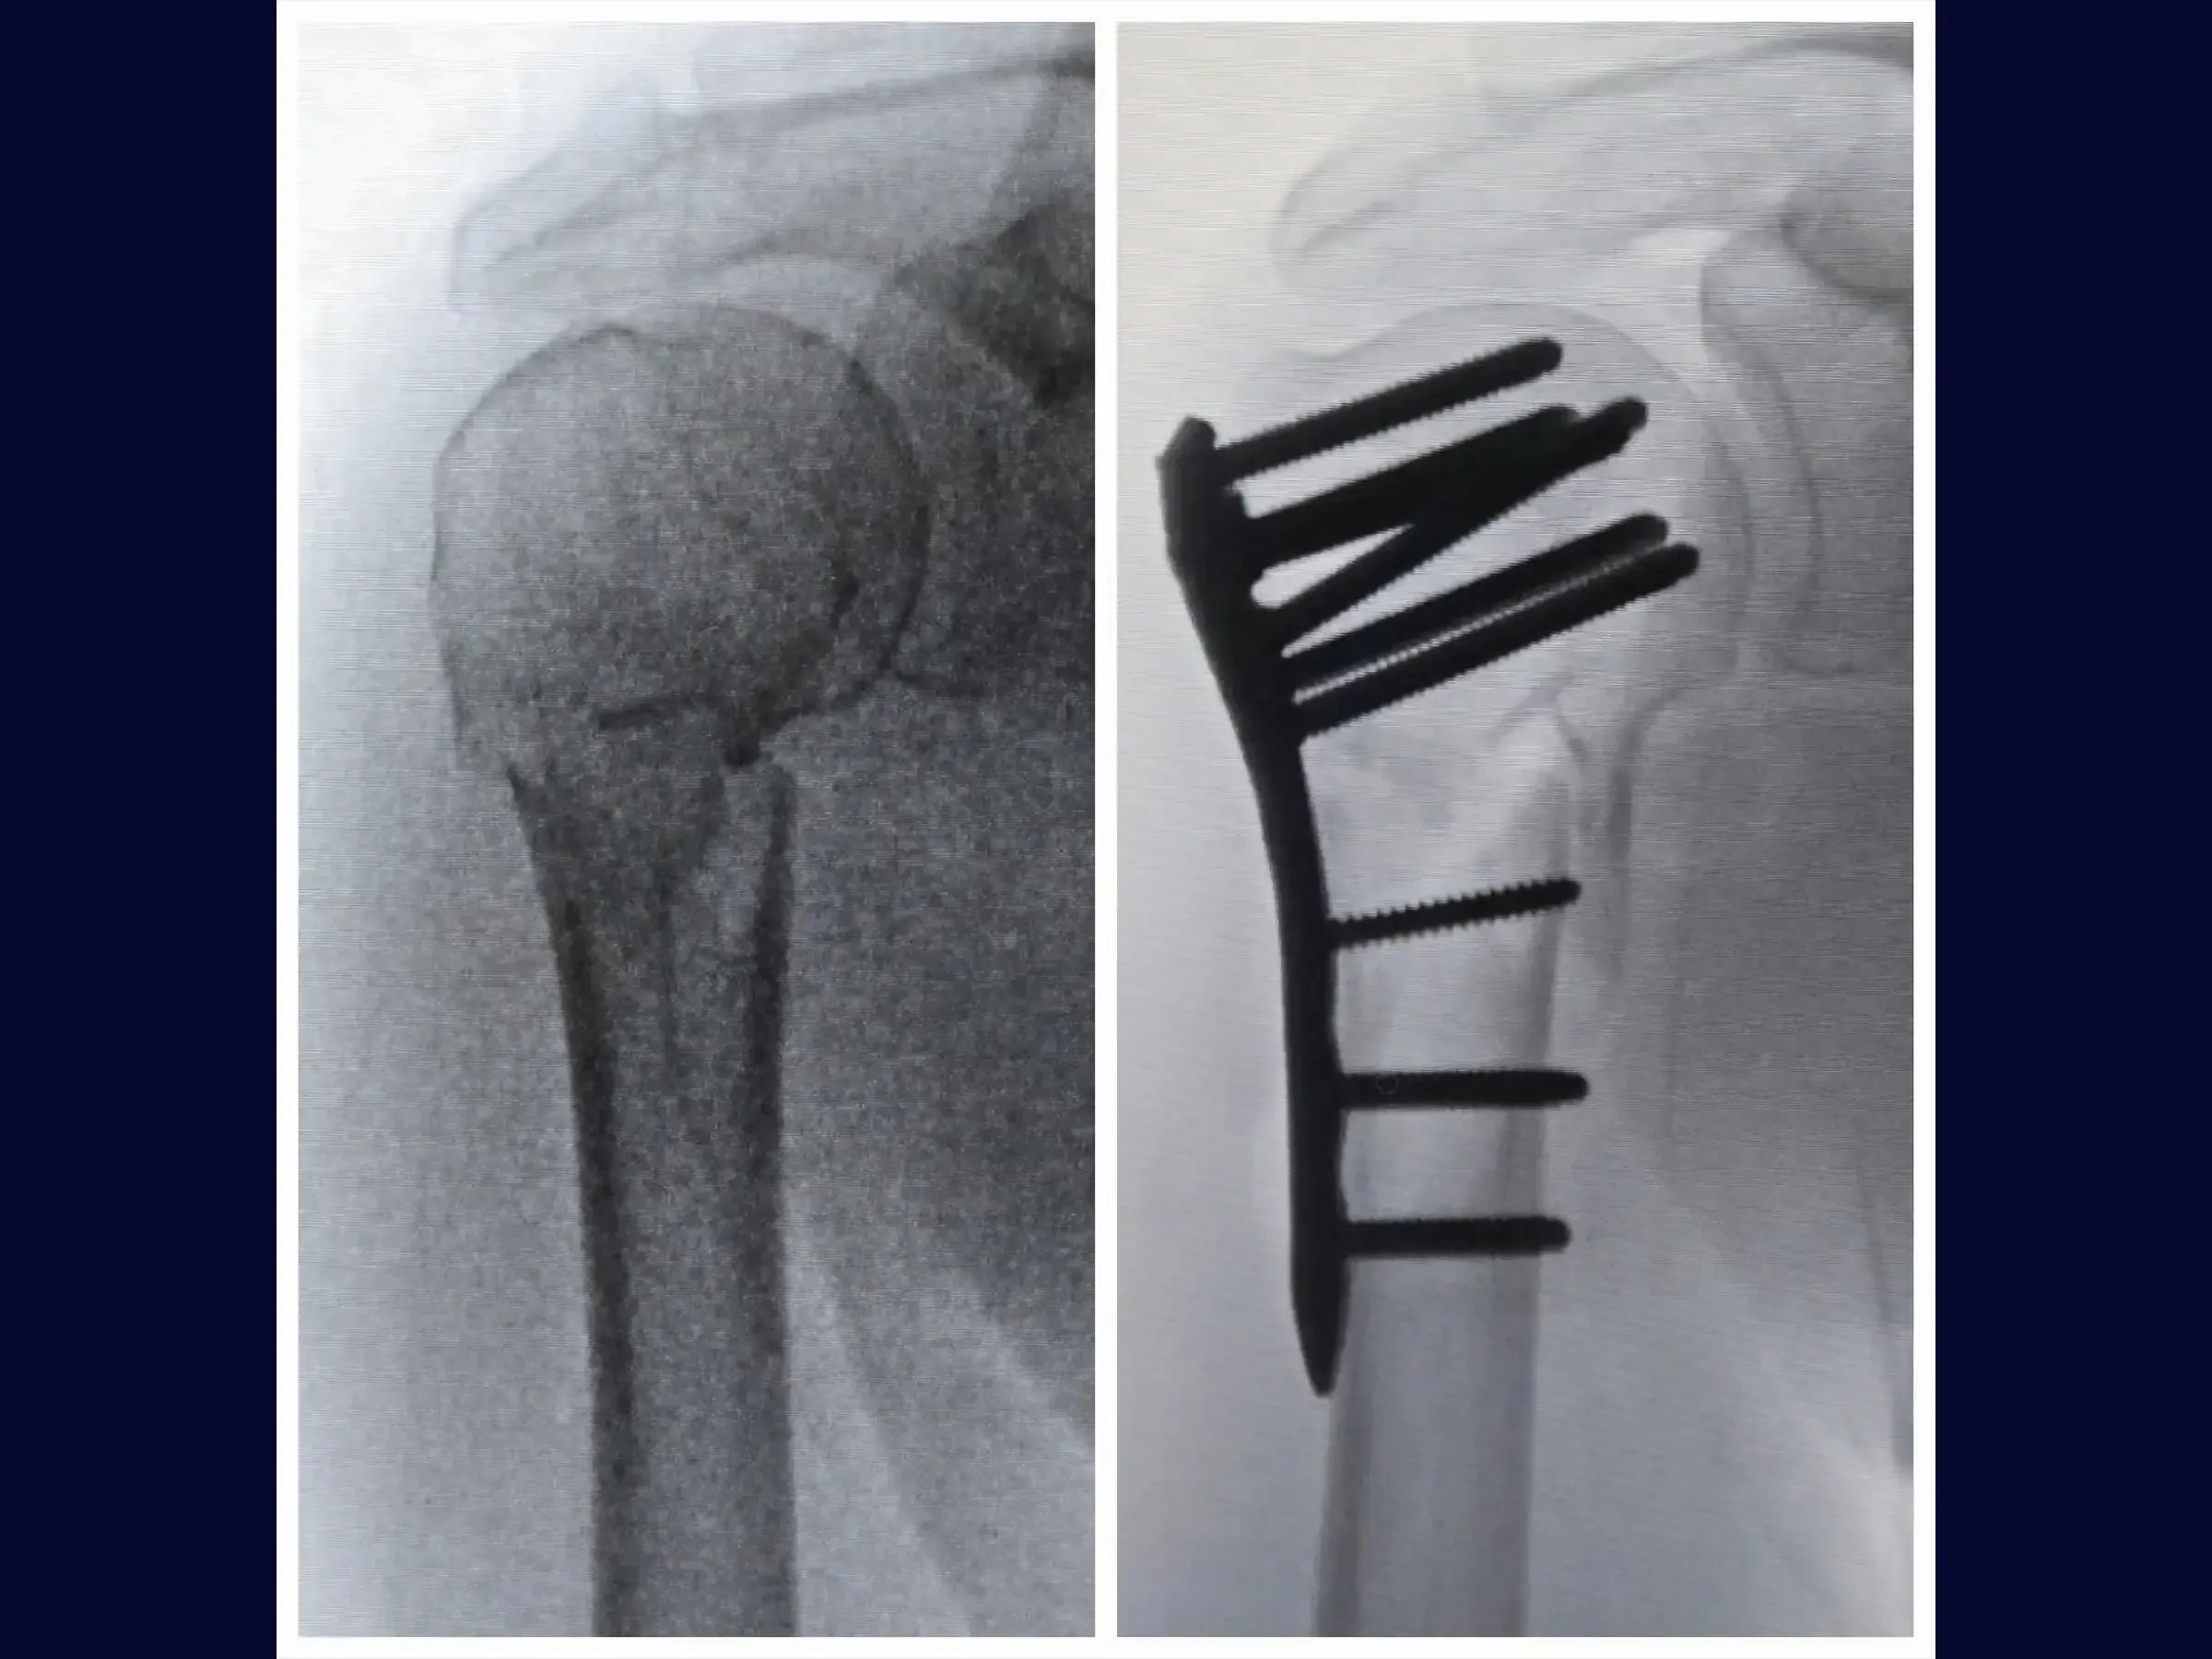

- Anatomical reduction of proximal humerus fractures and provisional fixation.

- Brocage technique and measurement of screws for definitive subchondral fixation.

- Refined Anatomical Reduction: Protocols for cleaning fracture vertices, identifying parameters such as the bicipital groove, and efficient provisional fixation.

- Secure Subchondral Fixation: Drilling methodology with sensitivity for precise positioning of screws in the subchondral bone, without perforating the cartilage, with initial insertion of the screws from the calcaneus.